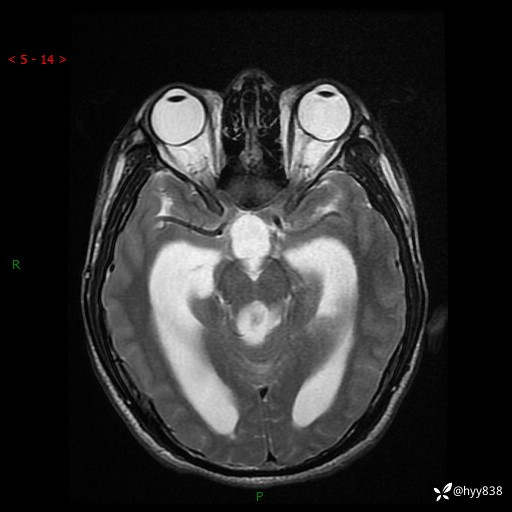

病例花季少年,头痛伴间断性呕吐1月余。四脑室占位,容易诊断错---结果公布~

性别:男

年龄:17岁

简要病史:头痛伴间断性呕吐1月余,外院CT提示颅脑占位

颅脑MRI平扫+增强